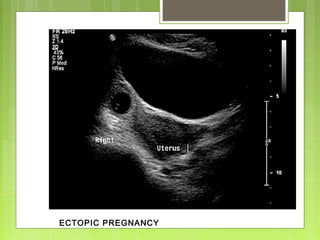

ECTOPIC PREGNANCY

Positive predictive value of 100% and a negative predictive value of

92% in women with a clinical suspicion of an ectopic pregnancy.

In combination with β-human chorionic gonadotropin - 96% of

ectopic pregnancies with a specificity of 100%.

If the β-hCG is at or above the discriminatory zone, AND no IUP can

be identified, the pregnancy may be ectopic

Ultra sound features :

Visualization of extra uterine G sac

Non specific, variably vascular, variably tender adnexal mass